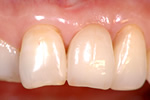

インプラント治療は、インプラントを骨に埋入することではありません。冠(かぶせもの)をして、しっかり咬めるようになることでで初めてインプラント治療をする意味があります。そのためには歯ぐきの治療、かみ合わせの治療など事前に行うべきことがあります。

当院では、質が高いゆえに材料費が決して安価ではないカルシテックインプラントを使用しています。被せものも優秀な技工士が製作することで自分の歯と見分けが難しいほどのものを装着することができます。その中で下記治療費で施術しております。